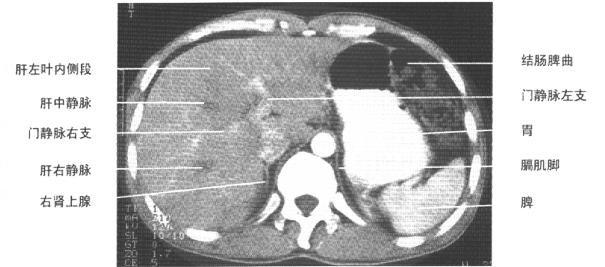

第二肝门层面(增强)